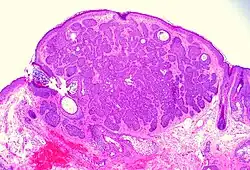

| Fibroepithelioma of Pinkus | Anastomosing epithelial strands in a fenestrated pattern[34] | Most commonly occurs on the lower back.[30]: 748 [31]: 648 |

![Fibroepitheliomatous pattern (anastomosing basaloid epithelial strands enclosing round islands of fibrous stroma)[36]](./_assets_/Micrograph_of_basal-cell_carcinoma_with_fibroepitheliomatous_pattern.jpg)